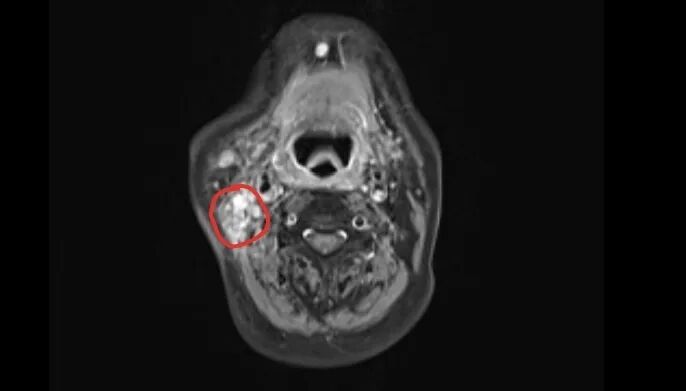

结果证实了张大伯的担忧:其右腮腺区及颈部有一个约4厘米×4厘米的肿大淋巴结,经穿刺活检确诊为鼻咽癌转移。

完成两个周期治疗后,影像复查显示,他颈部的转移淋巴结已明显缩小。目前,张大伯仍在继续接受治疗,他的脸上也重现了笑容:“多亏了毛主任和团队,让我又看到了希望。”